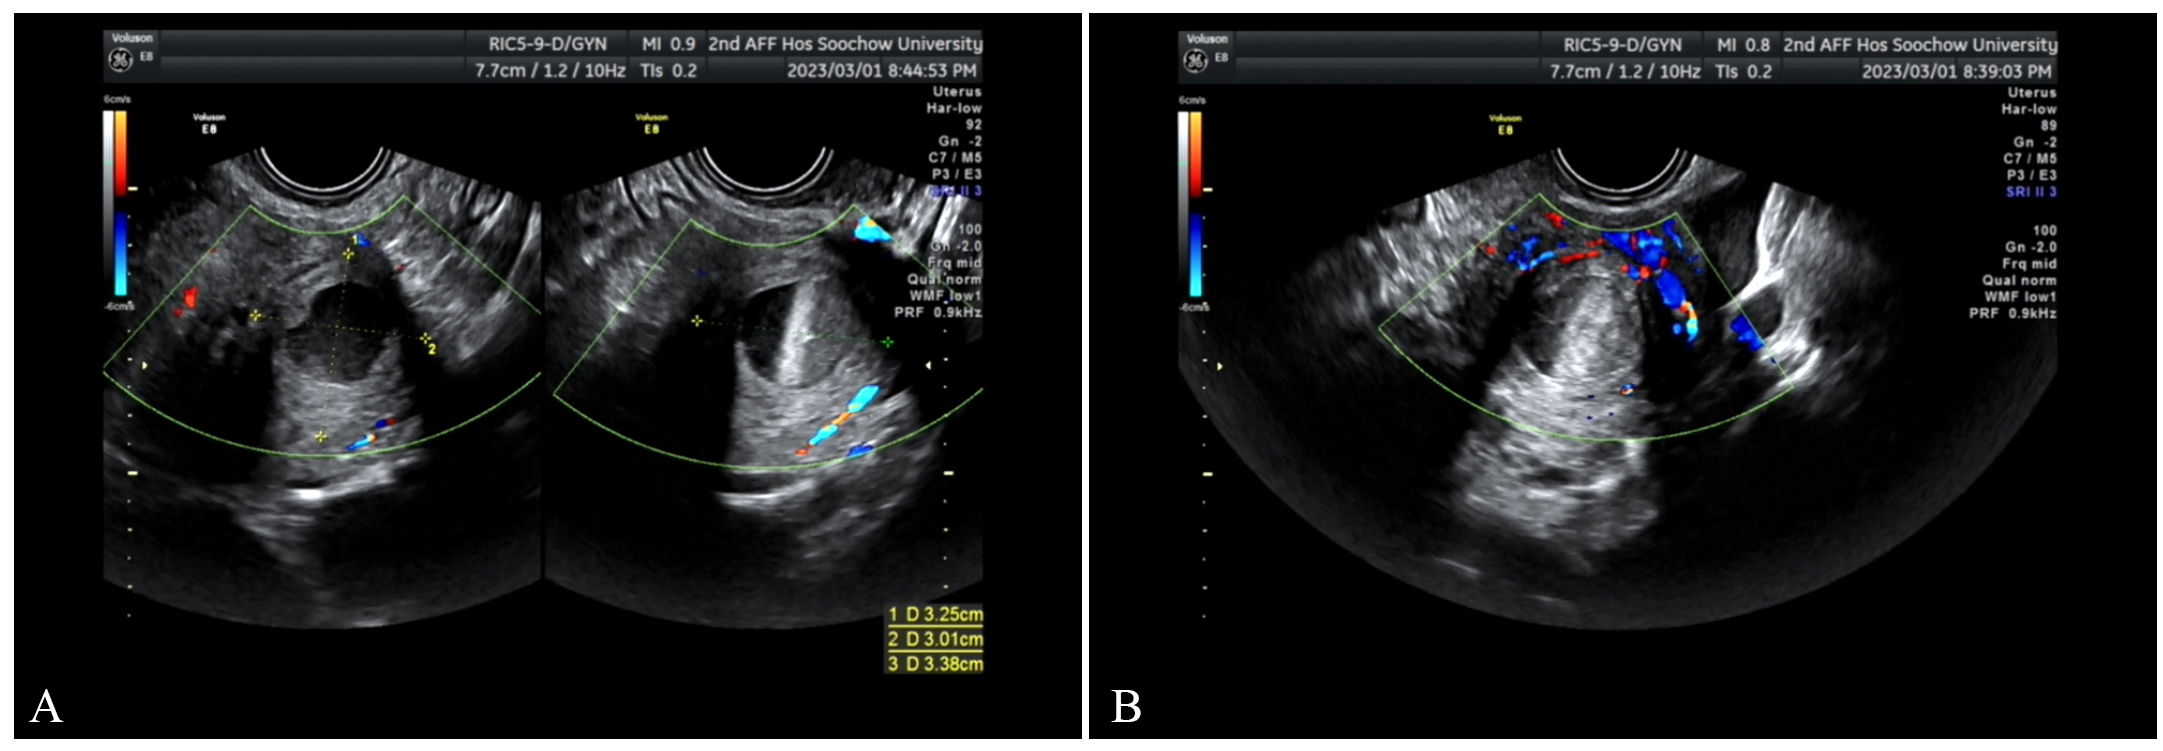

Fig. 3. March 1, transvaginal ultrasound scan. (A) The mass has enlarged compared with previous findings. (B) The surrounding blood flow signals have increased.